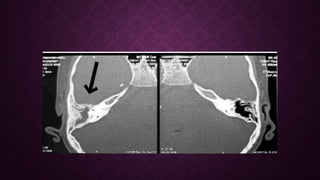

• Tomografia: Erosión/destrucción ósea

• Cultivo y tomografía de hueso temporal